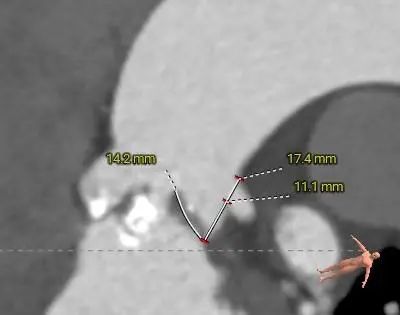

Type 0型二叶式主动脉瓣,左右冠脉同窦,重度钙化,左(右)冠窦和无冠窦内钙化弥漫分布于窦内,瓣叶对合缘存在局部钙化粘连及纤维增厚

冠脉开口高度可,左冠切线角度测量瓣叶长于LCA开口下缘到根部距离

主动脉瓣环水平夹角71度,严重横位心,主动脉弓宽度、角度尚可,弓部存在散在钙化